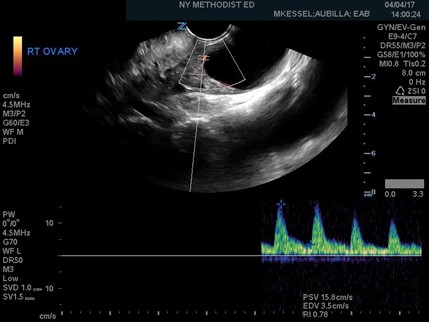

Once the gray-scale features have been delineated, Doppler flow can be utilized. Power Doppler should be used as it provides better sensitivity for slow or low blood volume states. Doppler findings will show either no blood flow to the ovary or asymmetric blood flow when compared with the other side. Once the power Doppler button is pressed, a gate will appear on the screen. The gate should then be placed over, and adjusted to, the size of the signal coming from the ovary. Once activated, a pulsed-wave Doppler tracing will appear on the screen. Arterial waveforms are pulsatile and have a high-flow pattern, while venous is typically continuous with minimal changes in the velocity of the flow. Resistance to arterial blood flow into the ovary, caused by outflow obstruction, can then be calculated by using the resistive index (RI). The RI is defined as the peak systolic velocity minus end diastolic velocity, divided by the peak systolic velocity, and is usually calculated using the ultrasound machine software on an arterial pulsed-wave Doppler tracing. A value of greater than 0.7, as depicted in Figure 3, indicates high resistance which is concerning for torsion.4

Figure 3. Ovarian torsion indicated by a high resistive index of 0.78